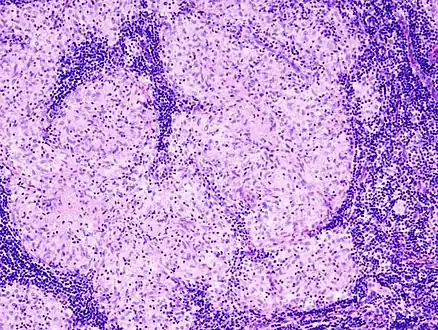

Histopathology

Sarcoidosis is characterized by the formation of non-necrotizing ("non-caseating") granulomas in various organs and tissues.[95] Giant cells, specifically Langhans giant cells, are often seen in sarcoidosis.[96] Schaumann bodies seen in sarcoidosis are calcium and protein inclusions inside of giant cells as part of a granuloma.[97] Asteroid bodies can be seen in sarcoidosis.[97] Hamazaki–Wesenberg bodies can be seen in lymph nodes and more rarely in lung biopsies with sarcoidosis and are inclusion bodies of lysosomes with protein, glycoprotein and iron.[98]

Sarcoidosis in a lymph node